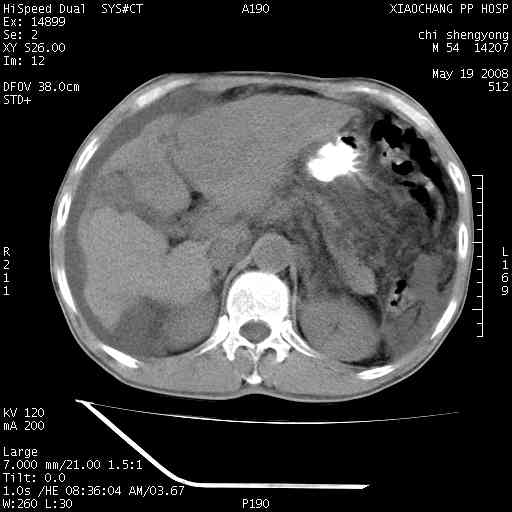

以下是引用zjzjr在2008-5-21 10:52:00的发言:[br]肝左叶巨块型肝癌伴门静脉左支瘤栓形成.肝硬化、腹水,胃底静脉曲张,脾术后改变。

以下是引用随光逐影在2008-5-21 16:20:00的发言:[br]1)肝左叶肝癌伴门静脉左支瘤栓形成,腹膜后淋巴结转移。2)肝硬化、腹水、胃底静脉曲张。3)胆囊炎。4)脾脏缺如,为切除术后所致。